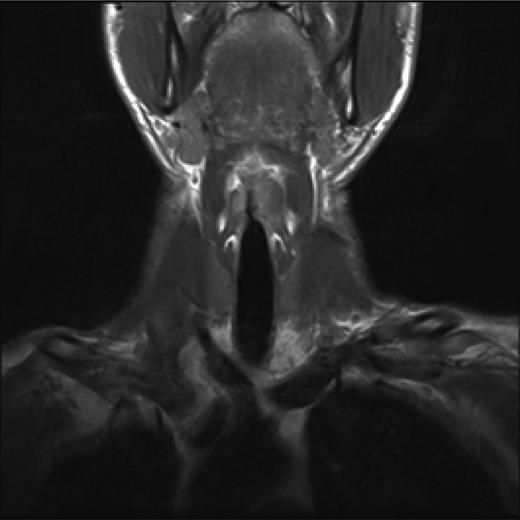

Post treatment with CO2 laser, the patient underwent a T1 weighted magnetic resonance imaging (MRI) with gadolinium of the neck. The imaging demonstrated an abnormal soft tissue density in the left supraglottic region (Figs 3 and 4). The low intensity lesion was 9 × 4 mm in size and caused distortion of the left aryepiglottic fold and minor airway narrowing. The findings on MRI suggested the persistence of disease.

Axial view of MRI neck demonstrating soft tissue abnormality in the left supraglottic area.